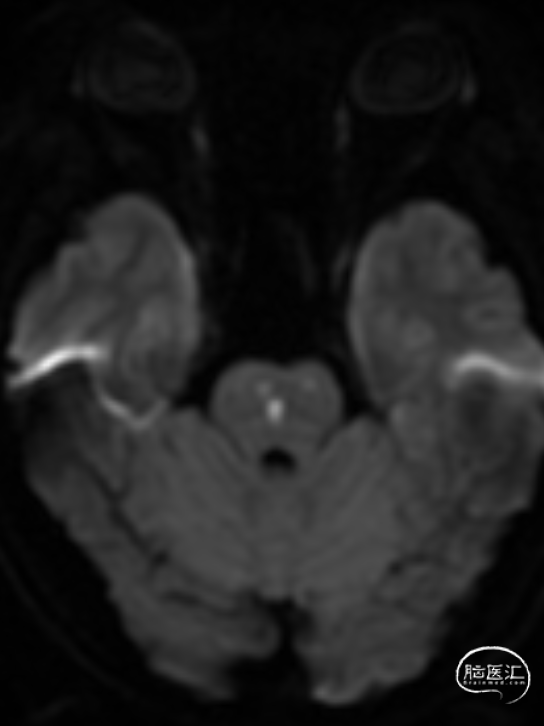

MR:双侧后循环散在急性梗死病灶(双侧小脑半球、双侧枕叶、胼胝体压部、右侧脑桥臂、桥脑右侧部及中脑被盖左侧)。MRA示:双侧椎动脉颅内段及基底动脉明显变窄。

举例图片,非上述病例患者